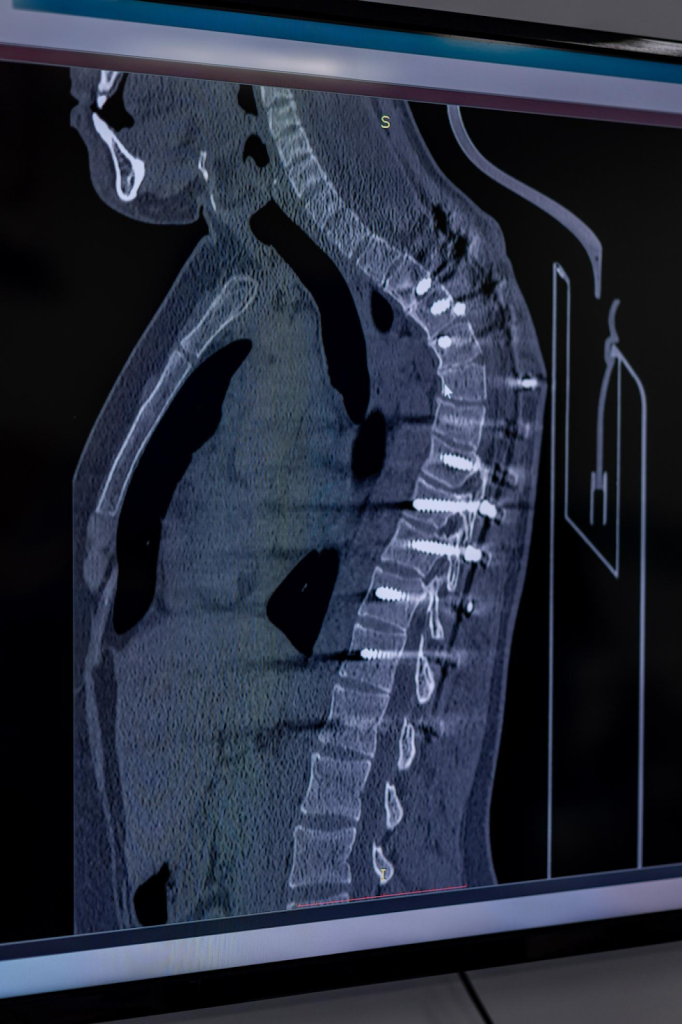

| Післяопераційний контроль металоконструкцій (гвинти, пластини) | КТ менше «спотворюється» через метал | МРТ дає виражені артефакти від металу |